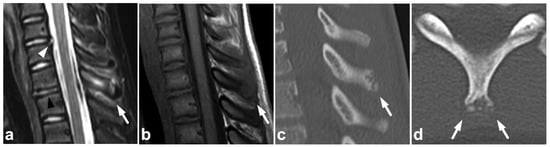

Acute clay-shoveler-type spinous process avulsion fractures are also seen, usually in teenage athletes [35]. On MRI, chronic stress fractures of the spinous process (sometimes called apophysitis of the spinous process) [36,37] may have a similar appearance to acute fractures. Chronic spinous process injuries are most abundant in the same type of population as acute fractures, but the symptoms usually follow a more gradual course. Targeted CT of the edematous spinous process helps to separate acute, sharp avulsion fractures from chronic injuries with sclerotic margins and fragmentation (Figure 5).

Figure 5.

(a) Sagittal STIR. (b) Sagittal T1-weighted. (c) Targeted NECT, sagittal reconstruction. (d) Targeted NECT, axial reconstruction. A 13-year-old male with neck pain after an ice hockey accident. MRI reveals significant bone marrow edema in the spinous process of Th1 (arrows). The surrounding soft tissues are also edematous. In targeted CT, the apophyseal region of the spinous process is fragmented without sharply lineated fracture lines. The findings are consistent with a chronic stress injury, perhaps exacerbated by the acute trauma. A dorsal annular tear and a small intervertebral disc protrusion are seen on level C6/7 (white arrowhead). Intervertebral disc Th1–Th2 is dehydrated and lower than adjacent discs (black arrowhead). These findings suggest degenerative changes.